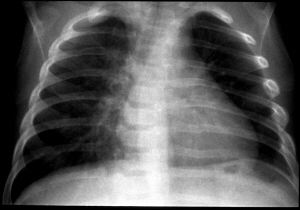

2. The paediatrician suspects shaken baby syndrome and order some

radiological investigations. The following pictures are consistent

with the suspicion: